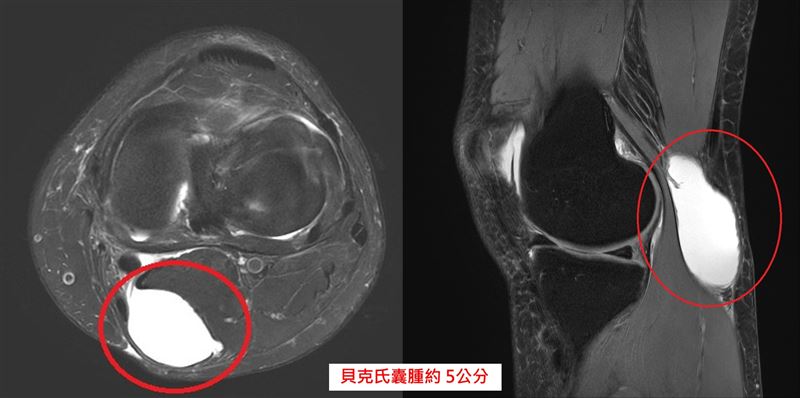

一名50歲女子近期覺得右腳後膝窩有異樣,摸起來像有顆「腫瘤」,甚至在上下樓梯、蹲跪時會出現壓迫感,嚴重時還會伴隨麻木感。就醫後診斷為「貝克氏囊腫」膕窩囊腫約5公分,最後手術切除。醫師提醒,平時應避免過度蹲跪,養成正確運動習慣,強化大腿肌肉,才能降低關節提早老化、反覆積水與囊腫生成的風險。

中國醫藥大學新竹附設醫院骨科醫師陳威仁表示,患者經診斷為「貝克氏囊腫」膕窩囊腫約5公分,經醫病溝通後,病人接受微創膝關節鏡手術治療,手術約30分鐘,術後隔天即可下床活動,2天後順利出院。